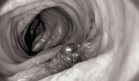

La fibrosis hepática, un proceso de cicatrización del hígado en respuesta a una lesión, es un paso previo a enfermedades hepáticas más graves, como la cirrosis y el cáncer de hígado.

Aunque no es una patología grave en sí misma, su detección temprana es crucial, ya que es un proceso dinámico y potencialmente reversible. Con este objetivo, un consorcio internacional de investigadores, liderado por el Hospital Clínic IDIBAPS de Barcelona, ha desarrollado un nuevo índice de riesgo llamado LiverRisk, que permite identificar la fibrosis hepática en personas asintomáticas de manera sencilla y no invasiva.